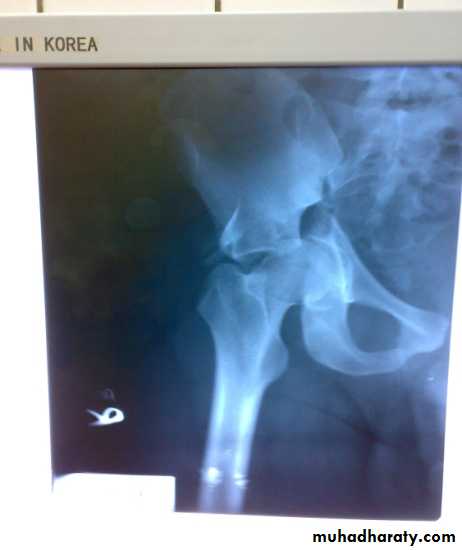

Fracture acetabulum

Fractures of the acetabulum occur when the head of the femur is driven into the pelvis.

This is caused either by a blow on the side (as in a fall from a height or road traffic accident ) or by a blow on the front of the knee, usually in a dashboard injury when the femur also may be fractured.

There is usually history of a severe injury; associated fractures are not uncommon and may divert the attention from the more urgent pelvic injuries. Whenever a fractured femur, a severe knee injury or a fractured calcaneum is diagnosed, the hips also should be x-rayed. The patient may be severely shocked. There may be bruising around the hip and the limb may lie in internal rotation (if the hip is dislocated).

Neurological examination is important, testing the function of the sciatic, femoral and obturator . Several X-ray views of the hip are needed to visualize the fracture accurately. CT scans are particularly helpful if surgical reconstruction is planned.